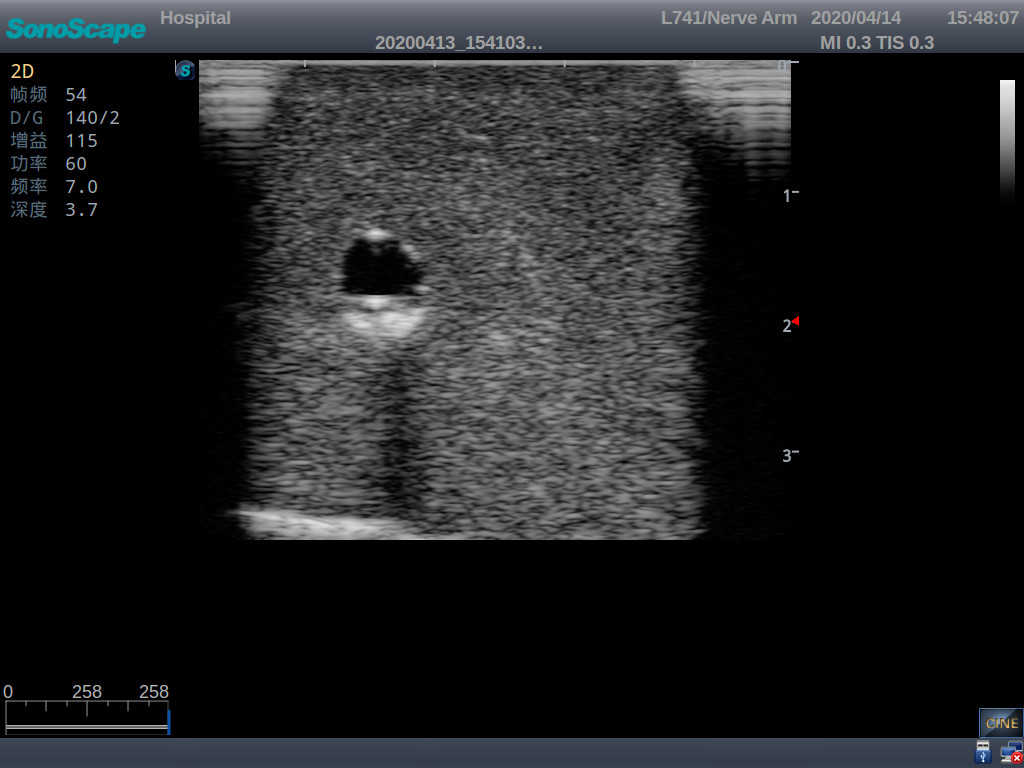

PICC Ultrasound Training Model

Model TYE1510.1

Outline

It is a model covering up from lobulus auriculae plane to the umbilical plane, and it has anatomical structures like clavicle, rib, sternocleidomastoid, jugular vein and basilic vein.

Features

1)   Made of high molecular polymer ultrasound material, close to the real skin

2)   It can be used by real ultrasound machines

3)   Clear and real images of the tissues and organs (basilic vein and superior vena cava)

4)   When conducting vascular puncture, the piercing can be truly felt, and venous blood outflow can be seen

5)   Observe the guide wire marches

6)   Detect whether the catheter is properly placed